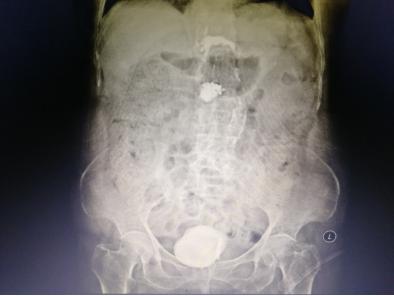

入院后,经过专业的全面系统检查后,我院泌尿外科专家组针对李老太病情召开了联合会诊。李老太的结石犹如鹅蛋般大小,而且已引起一系列严重并发症,不及时取出结石将造成更严重后果,对于一个91岁高龄而且身体情况欠佳的老太太来说采取哪种手术方案都有弊有利。

暨南大附属一院泌尿外科卓育敏主任分析:“为她选择治疗方案的时候必须慎重,因患者年龄大,多项器官功能都有明显衰退而且膀胱已无多少操作空间,开放手术虽很快可以完成,但一个7-8公分的伤口对她来说就是一个很大的创伤,很容易发生脂肪液化,尿漏等并发症,这对老人都可能造成不可预测的影响。而采用经尿道手术近乎无创,但这种结石最坚硬,又那么大,手术时间肯定很长,医生累且不说,一台高功率碎石机连续多小时的工作可能都扛不住会死机,要准备2台机器轮番上阵,要避免器械对老太膀胱黏膜损伤。”